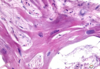

How long post-infarction and what type of infection do you see in this image?

*

A biopsy of a patient’s infarcted tissue is shown below. How long has it been since the infarction?

4-24 hours. Note absence of nuclei and neutrophils.

What is this patient at risk for if the infarcted tissue was a transmural infarction?

Fibrinous pericarditis. Note the neutrophil infiltrate indicating it has been less than one week since the infarction?